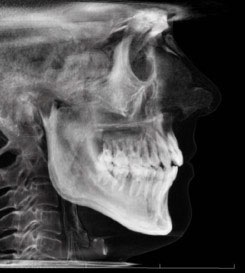

The extraoral examination revealed a long facial type with an increased lower facial third, nasolabial folds accentuated by insufficient midface support, and broad buccal corridors due to maxillary compression. Intraoral analysis showed a posterior crossbite, negative torque on posterior teeth, and an altered occlusal balance. Radiographic and cephalometric evaluation confirmed the clinical findings, with an increased mandibularplane angle and mandibular posterior rotation. This rotation contributed to a convexity of +4 mm, although the underlying problem was a retruded maxilla with insufficient midface support. Vertical facial height was also increased. Importantly, the temporomandibular joint evaluation showed a posterior condylar position with intact cortical bone, no pain, and no joint sounds.